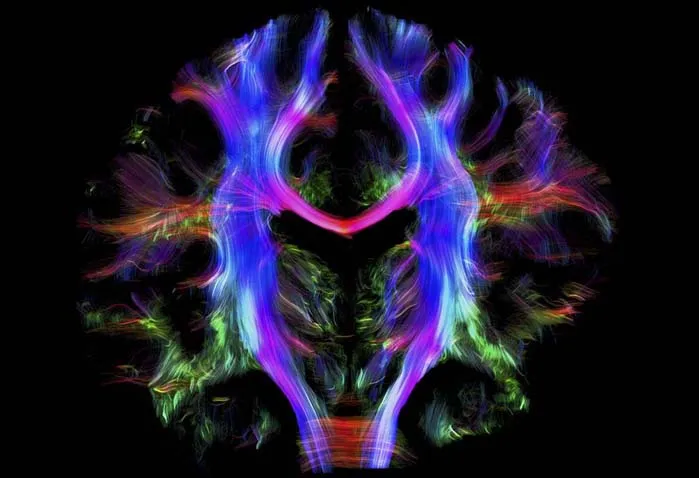

سیمپیچی مغز انسان

این زیبابین رنگی (kaleidoscope) نقشهای از درون مغز یک فرد جوان و سالم را نشان میدهد. قسمتهای مختلف مغز از طریق فیبرهای عصبی با هم ارتباط برقرار میکنند. در این تصویر فیبرها با رنگها نمایش داده شدهاند.